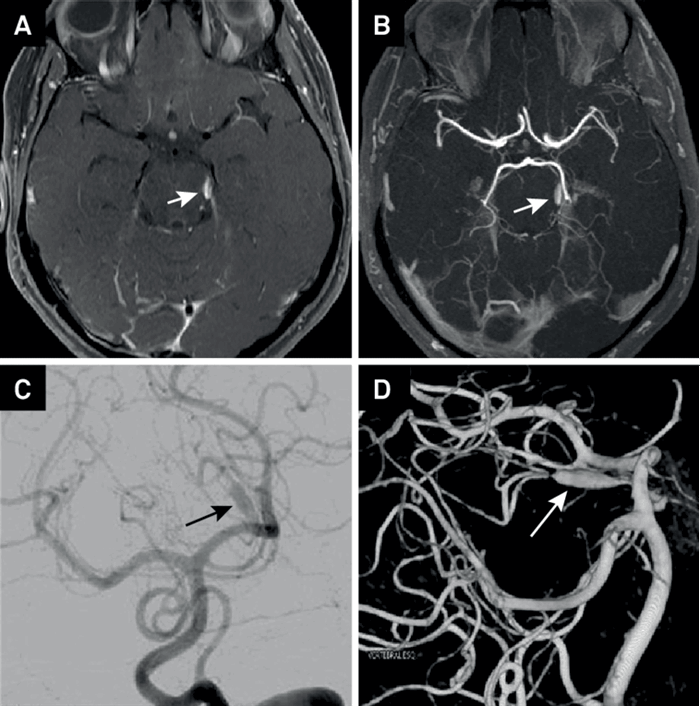

- На МР- и субтракционных ангиограммах имеет характерный изгиб, напоминающий «шпильку для волос»

Методом выбора является МРТ с контрастным усилением, с получением диффузионно-взвешенных изображений. Наиболее значимый диагностический признаком является гиперинтенсивность паренхимы спинного мозга на Т2-ВИ с центральной зоной напоминающий «совиный глаз». Гиперинтенсивность центрального серого вещества спинного мозга в Т2-режиме, изменения периферических участков паренхимы спинного мозга более вариабельны.

МР-ангиография

Динамическое исследование с контрастным усилением выполняется для исключения других патологий, которые могут напоминать инфаркт, например, дуральной артериовенозной фистулы. Малоинформативна в отношении диагностики тромбоза передней спонномозговой артерии, поскольку отсутствия контрастирования передней спинномозговой артерии на МР-ангиограммах недостаточно для подтверждения диагноза.